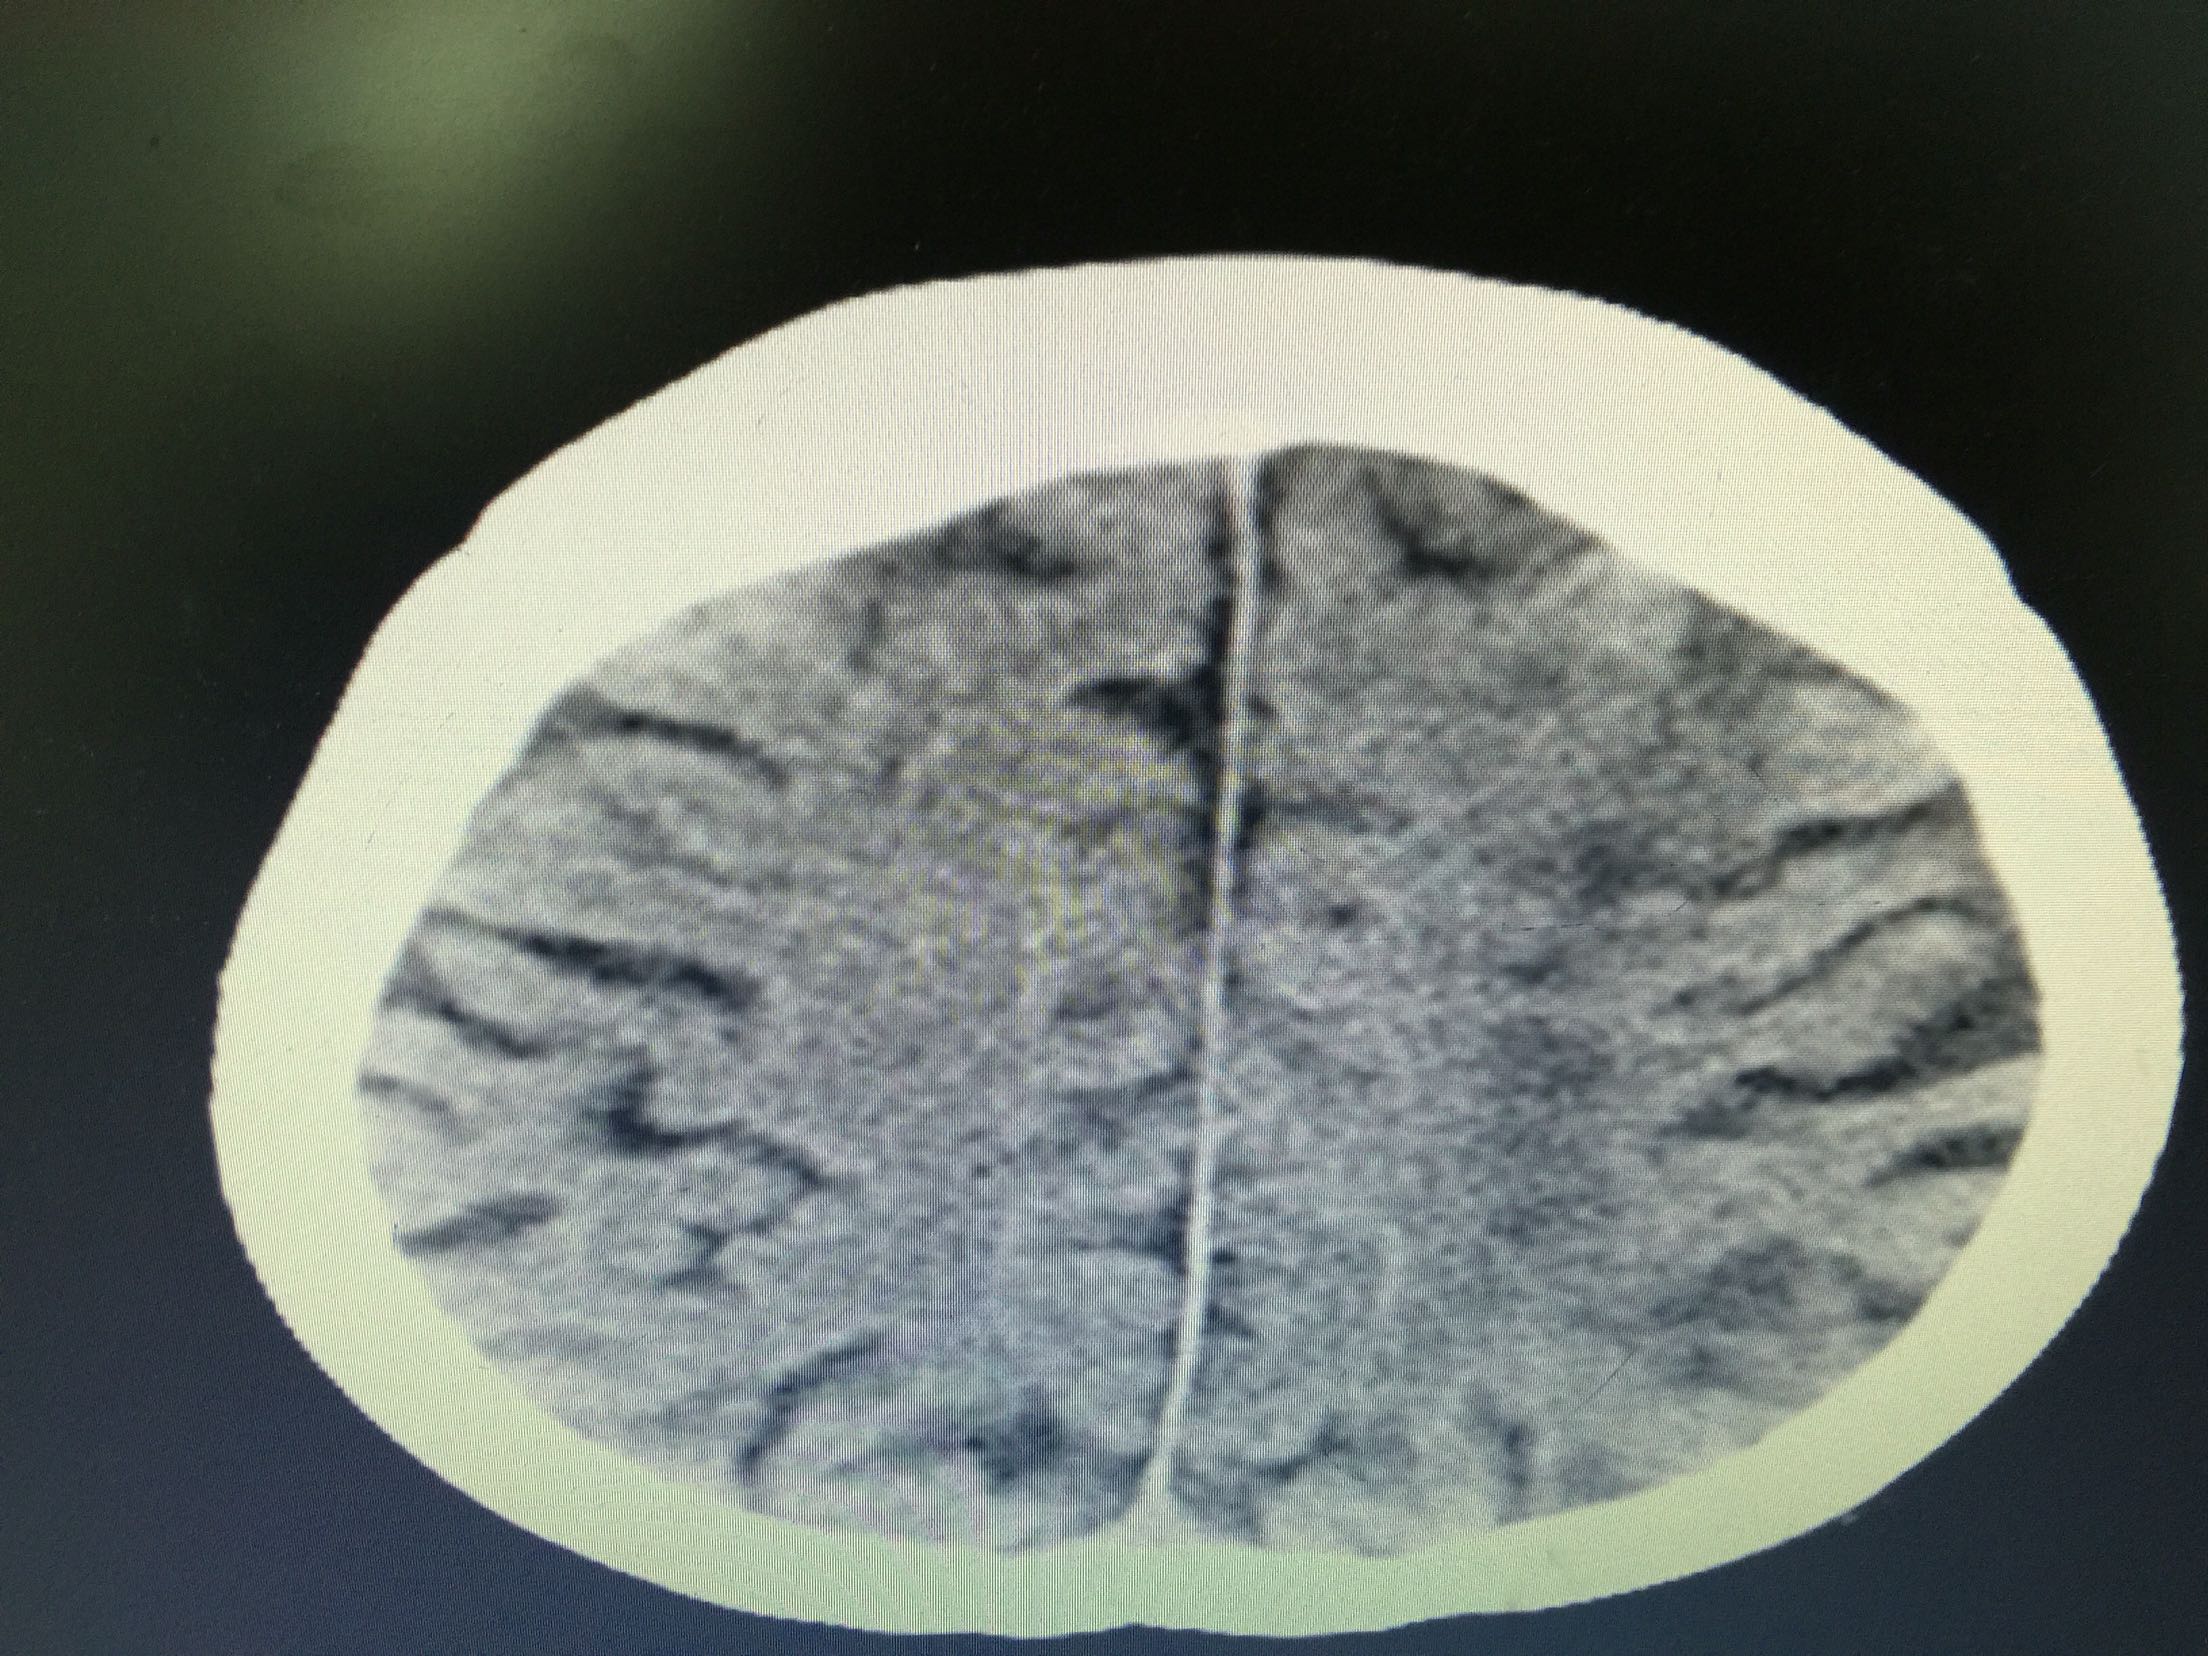

分水岭梗塞1例!

女,86岁,以“嗜睡、右侧肢体无力20小时”入院。 现病史:20小时前无诱因出现嗜睡,可唤醒,问话可答,不理解含义,右侧肢体无力。 既往史:高血压。

查体:血压:136/80mmHg,意识清,不全运动性失语,右侧中枢性面瘫,右侧肢肌力1级,Babinski征左-右+。

诊断:分水岭梗塞! 治疗:扩容、抗板、稳定斑块、促进侧枝建立等治疗。